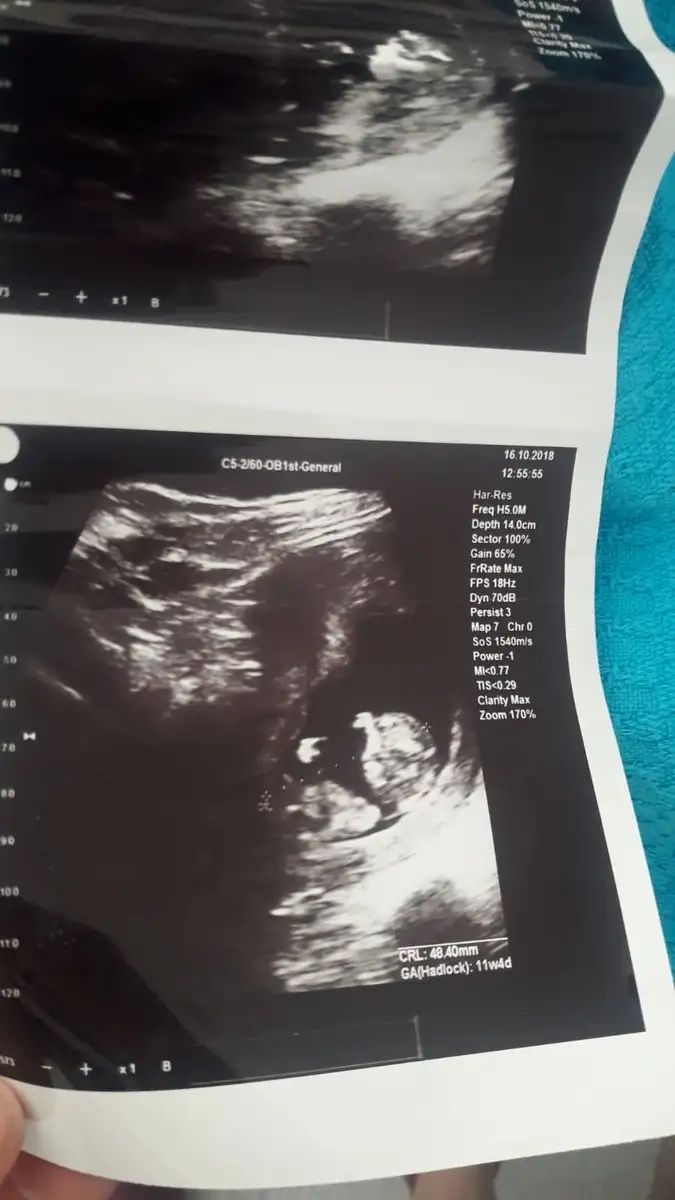

14 haftalik canim ama devlette biraz daha ileri cikti . Ozel doktoruma gore soyluyorum. Insallah canim. Insallah tez vakitte sizde saglik ve hayirlisi ile gorursunuz . Ve hepimiz de kucagimiza hayirlisi ve saglikla aliriz insallah . Erkege kiza nasil benzetiyosunuz o kadar baktim nesinden anliyosunuz :))))